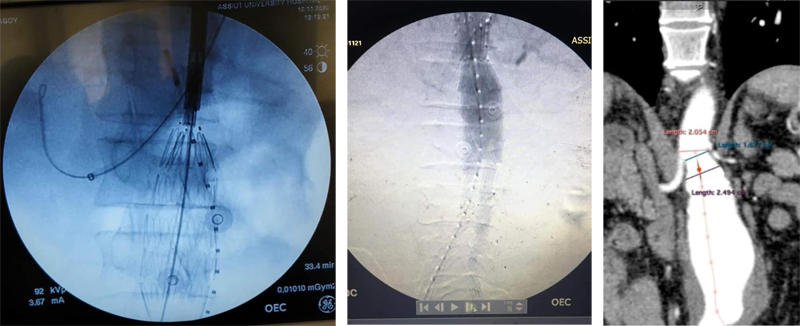

مناقشة رسالة الدكتوراه الخاصة بالطبيب/ محمد السيد أحمد عرفة - المدرس المساعد بقسم جراحة العظام